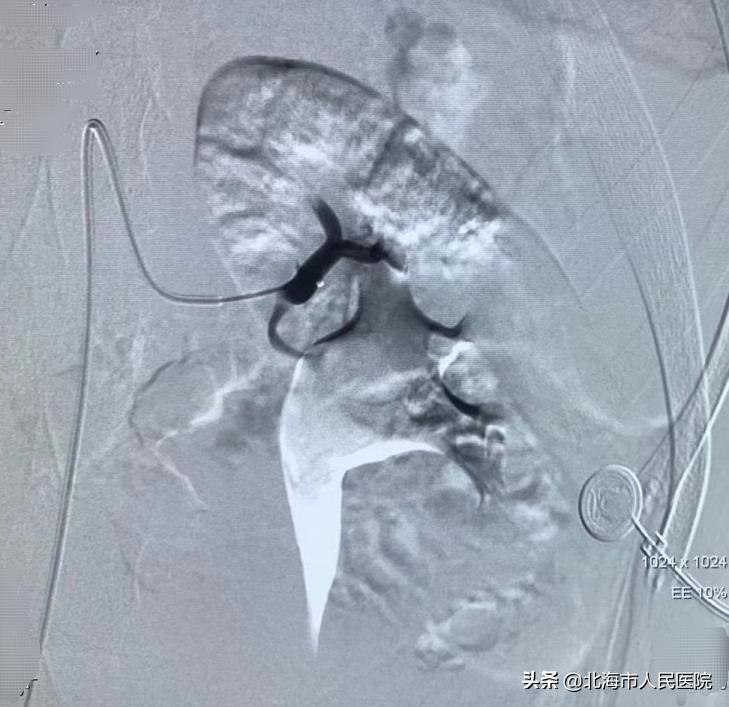

根据年轻患者的具体情况,需要考虑在手术止血的前提下尽量多保留患者的肾功能。

6月20日下午,张成文在刘建超医生的配合下,通过微创介入手术的方式,在患者的右大腿股骨沟动脉处进行穿刺,行肾动脉栓塞术,顺利为患者止血,成功保住了患者的肾脏。手术经历一个小时顺利完成,患者的血尿立即停止,无明显不适。